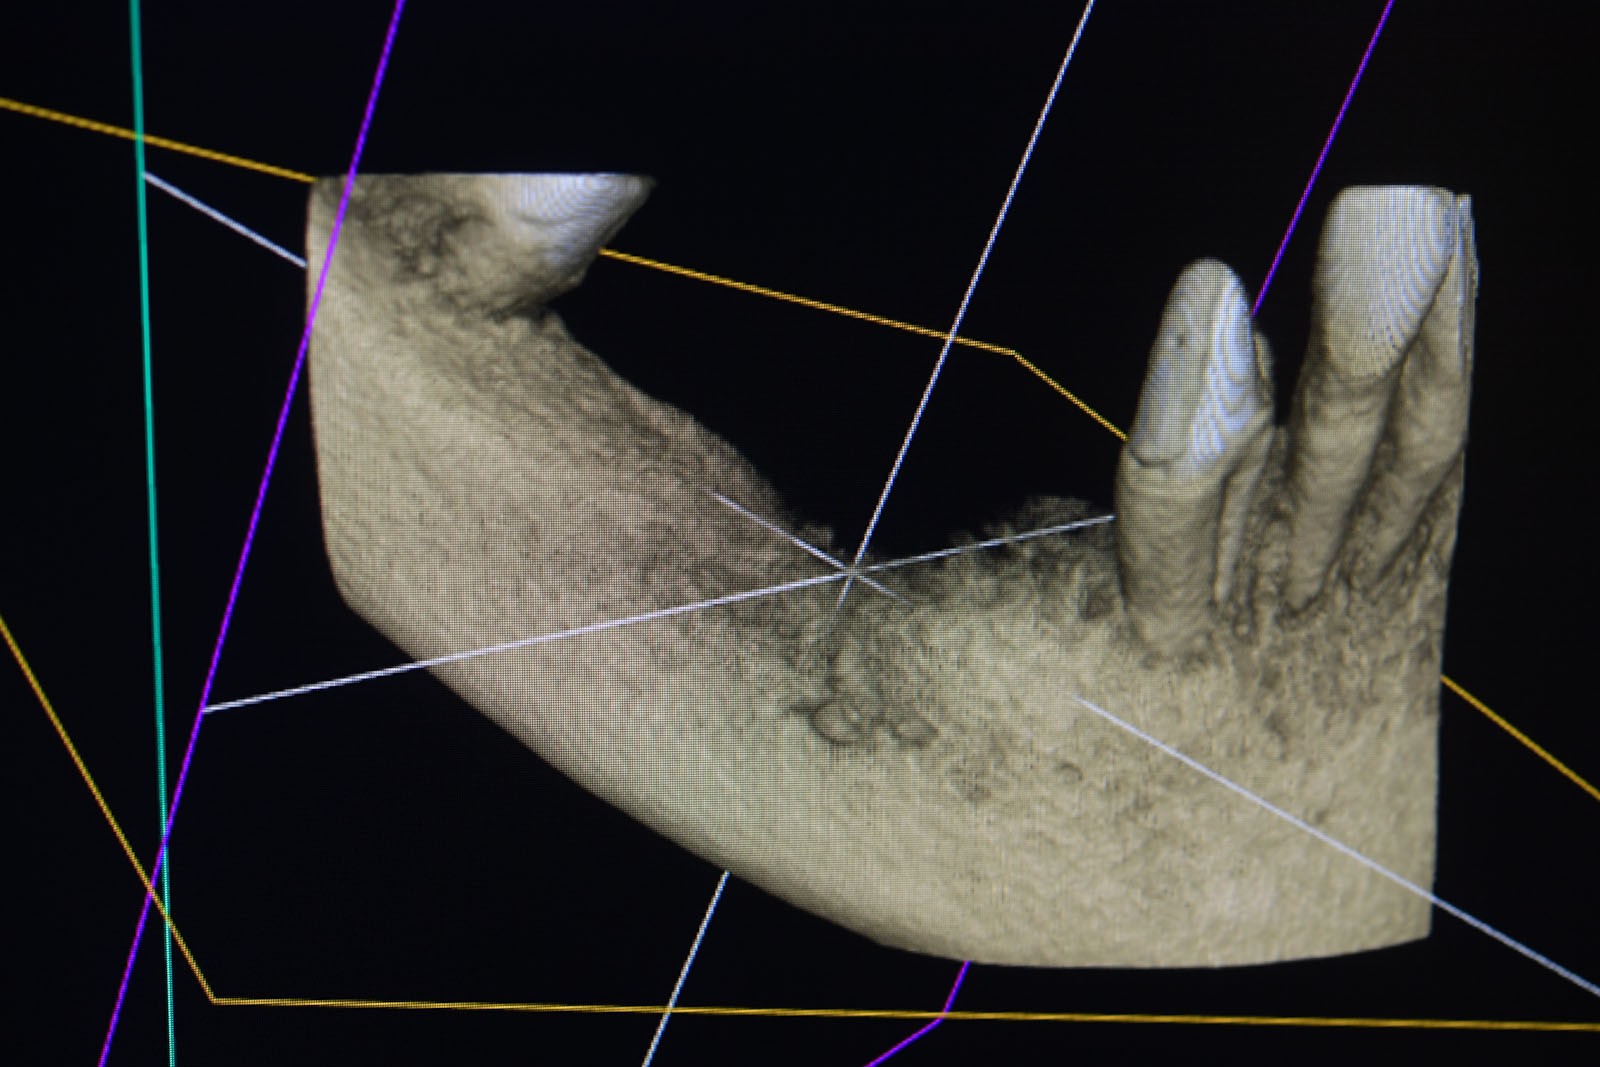

To kolejna metoda umożliwiająca precyzyjną odbudowę zadanego kształtu tkanki kostnej przy użyciu standardowych materiałów kościotwórczych, kości własnej lub PRF oraz zewnętrznego rusztowania w postaci siatki z biozgodnego stopu tytanu. Siatka jest indywidualnie projektowana w technologii CAD CAM i następnie drukowana dla konkretnego przypadku.

Dotychczas stosowane stabilizatory zewnętrzne w formie siatek tytanowych używane do regeneracji kostnej lub w zabiegach odtwórczych w chirurgii szczękowo-twarzowej uwzględniały materiały ręcznie doginane i formowane podczas zabiegu operacyjnego. Zastosowanie technologii CAD CAM dla potrzeb druku materiałów przeznaczonych do indywidualnej rekonstrukcji kostnej znacznie poprawiło precyzję i jakość uzyskiwanych efektów. Wdrożenie biozgodnych stopów tytanu do druku siatek zdecydowanie ograniczyło odsetek powikłań zapalnych.

Siatki stanowią stabilną obudowę – ograniczenie nadające kształt regenerowanej kości przy użyciu upakowanego pod nią materiału. Utrzymują i stabilizują rozdrobniony granulat kościotwórczy, co jest warunkiem prawidłowego procesu gojenia, jednocześnie nadając anatomiczny kształt i zakres odbudowie kostnej sprzed jej zaniku.

Precyzja projektu druku siatki bazuje na dokładności odwzorowania kształtu kości w stożkowej tomografii komputerowej CBCT, co zapewnia ich dobre przyleganie do podłoża kostnego oraz ogranicza powstawanie powikłań w postaci obnażania się siatek.

Precyzja projektu oraz materiał, z którego wykonana jest siatka (biozgodny stop tytanu), powodują, że obnażenie się siatki nie zaburza procesu gojenia i regeneracji kostnej. Wymaga jedynie większej ilości kontroli pozabiegowych oraz wzmaga czujność higieniczną zarówno ze strony lekarza, jak i pacjenta.

Ten rodzaj odbudowy kostnej stosowany jest w sytuacjach złożonych, trójwymiarowych 3D ubytków kości, przy których standardowe metody odbudowy są niewystarczające. Ilość kości, którą możemy uzyskać, stosując tę metodę, to nawet kilka centymetrów sześciennych.

Metoda rekonstrukcji kostnej w oparciu o indywidualnie drukowane siatki z tytanu dla implantacji wszczepów śródkostnych stosowana jest najczęściej jako dwuetapowa. W pierwszym etapie odbudowywana jest kość, natomiast implanty wszczepiane są po okresie 4–6 miesięcy. Na wgojenie implantów oczekujemy od 4 do 6 miesięcy w zależności od miejsca ich lokalizacji. Siatka tytanowa po spełnieniu swojej funkcji rusztowania dla odbudowującej się kości jest następnie usuwana w dniu wszczepienia implantu. Jeżeli kość spełnia odpowiednie warunki, istnieje możliwość zastosowania modyfikacji siatki tytanowej, która umożliwia jednoczesne wprowadzenie implantów wraz z odbudową kostną. Wariant ten skraca czas od pierwszego zabiegu do wykonania gotowych koron protetycznych na wprowadzonych implantach.